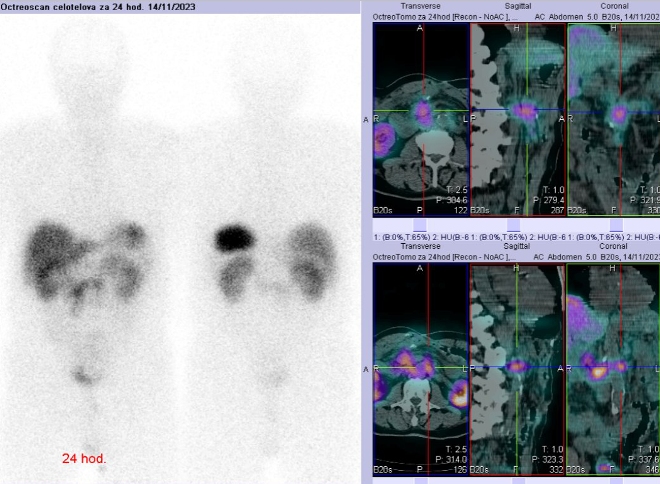

Scintigrafie Octreoscanem:

I. v. jsme aplikovali 190 MBq analogu somatostatinu značeného 111In

(přípravek OctreoScan firmy Curium Netherlands

B.V.) a provedli pomocí hybridní tomografické scintilační kamery Symbia T2 firmy Siemens opatřené kolimátory pro střední energie planární celotělovou scintigrafii a cílenou tomografickou scintigrafii (SPECT) břicha a pánve kombinovanou s CT za 4 a 24 hod.

(obr. 1-3).

/ Obr. č. 1: Celotělová scintigrafie 4 a 24 hod. po aplikaci OctreoScanu.

Popis: Prokazujeme dva okrsky patologicky zvýšené hustoty somatostatinových receptorů v paketu LU na mesenteriu vpravo ve výši L2 a v LU v retroperitoneu paraortálně vlevo ve stejné úrovni - svědčí nejspíše pro metastázy NET.